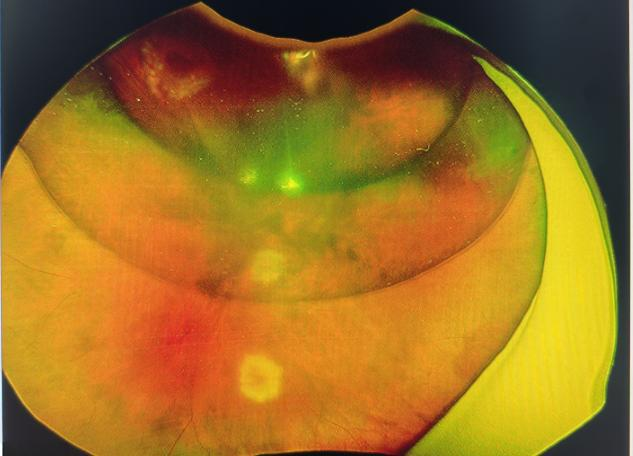

术前的视网膜

杜磊主任在明确视网膜脱离的范围、裂孔的大小及位置,以及玻璃体的状态后,迅速制定了最佳手术方案:左眼视网膜脱离修复及玻璃体腔气体填充手术。这一方案不仅能够修复视网膜裂孔,还能通过气体填充辅助视网膜复位,最大限度地挽救高先生的视力。

高先生术后气体填充后的视网膜